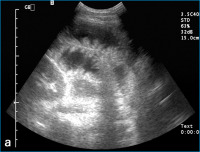

Dünndarmschlingen

Abbildung 3a: Sonographische Darstellung massiv flüssigkeitsgefüllter Dünndarmschlingen mit starrer Darstellung der Kerckringschen Falten, dem sogenannten "Klaviertastenphänomen".

Keywords: DünndarmschlingenKerckringschen FaltenSonographie

Aszites

Abbildung 3b: Aszites im Spatium hepatorenale (Pfeil).

Keywords: AszitesSonographieSpatium hepatorenale